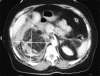

We report a case of Wunderlich's syndrome in an obese woman associated with massive retroperitoneal hemorrhage. Stable hemodynamic patient condition was obtained by selective arterial embolization. Since the first embolization of a renal angiomyolipoma in 1976 by Moorhead et al., highly selective renal arterial embolization of angiomyolipoma with rupture has become a procedure that offers greater efficacy, particularly in life-threatening cases.